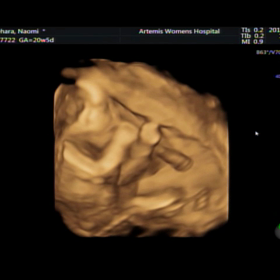

20w5d 3D4Dエコー エコー検査 COMME CA BLANC D'OEUFのマタニティウ